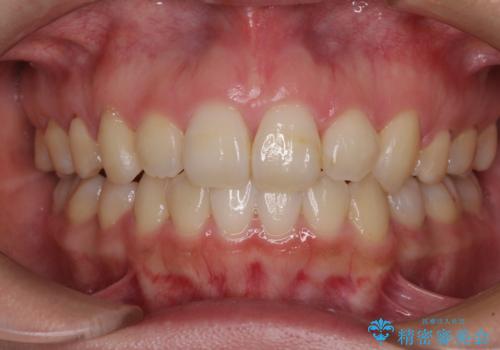

- 口元の突出感を気にして来院された患者様です。

診断の結果、上顎左右第一小臼歯4本抜歯により、叢生を解消するとともに口元を引っ込めていくことが望ましいと判断しました。

抜歯矯正による口元の改善にはワイヤー矯正が望ましいのですが、ダンサーとしての仕事を行っているため、インビザラインにて治療を行うこととしました。